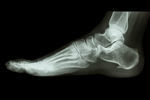

足底筋膜炎

【症例】足底筋膜炎

レントゲン検査は異常なし、足底筋膜炎と診断されますが「疲労ですね」と言われ、安静にしている様にドクターから指示を受けます。